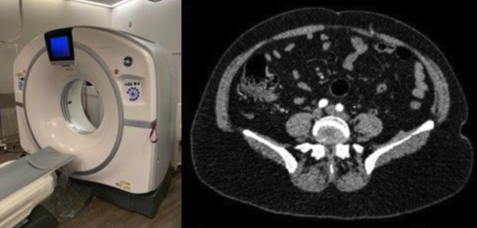

Considered one of the leading preoperative imaging modalities for breast reconstruction, CTA was first described by Masia et al and is currently the gold-standard modality for vascular mapping for ABBR.12 CTA has largely replaced previous imaging modalities for breast reconstruction due to its ability to create a real time 3-dimensional (3D) model of a branching network, an advancement over the 2-dimensional (2D) models produced by HDU and CDU (Figure 3). One of the earliest studies reported that CTA was capable of accurately localizing 100% of perforators within the patient cohort (22 of 22) compared with HDU, which was unable to localize 1 (0 of 22).24

Unlike HDU and CDU, CTA’s 3D image is produced by injecting an intravenous (IV) contrast medium before imaging, allowing this technology to reconstruct trilateral images8 with diagnostic accuracy of 100% for perforators over 1 mm.25 CTA is capable of identifying a perforator’s course (ie, intramuscular, subfascial, or subcutaneous) and its respective branching network, making CTA an extremely powerful perforator mapping modality.25,26 Other reported advantages include decreased dissection time, ability to reveal the anatomical relationship of any perforating vessel and its branching network, and increased patient comfort when undergoing this imaging compared with that of previously used modalities. Unlike predecessor imaging methods, CTA images can be obtained while the patient is in the supine position, and patients are required to hold their breath only once to retrieve the scan.27 CTA has also been proven useful in postsurgical evaluation of changes to the vasculature.28